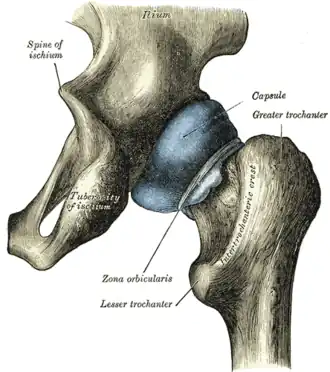

Structures surrounding right hip-joint

Structures surrounding right hip-joint -